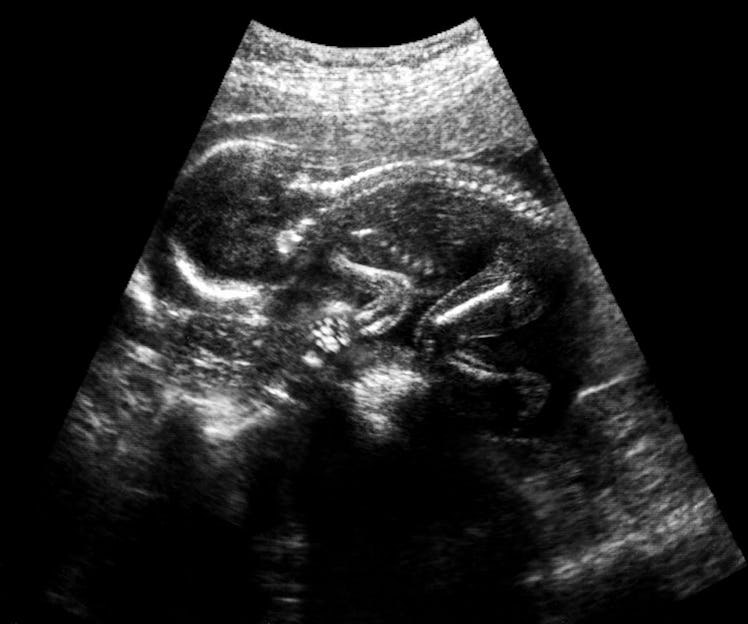

It’s clear that, based on real-time fetal ultrasounds, babies in utero experience typical sleep cycles that include periods of both REM sleep and non-REM sleep. One of the first studies to observe fetal REM was published in the journal Early Human Development in 1992 by Japanese researchers. The scientists found that rapid eye movement was detectable between 28 and 30 weeks of gestation and that the periods of REM sleep increased as the pregnancy progressed.